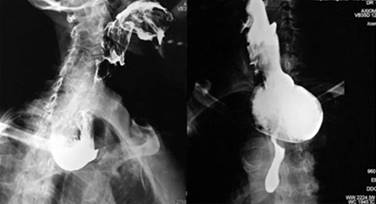

A todos los pacientes se les tomaron datos clínicos demográficos, tales como: edad, sexo, tiempo de evolución de los síntomas y síntomas predominantes, características del divertículo, remisión de los síntomas y necesidad de reintervención. El diagnóstico de divertículo de Zenker se realizó por medio de estudio radiológico de contraste (esofagograma con medio de contraste baritado) y endoscópico, con lo cual se confirmaba el diagnóstico y se calculaba el tamaño del divertículo (Figura 1).

Figura 2: Introducción de guía metálica a esófago como primer paso y posterior colocación de dilatador de Savary Gilliard para delimitar septum diverticular.